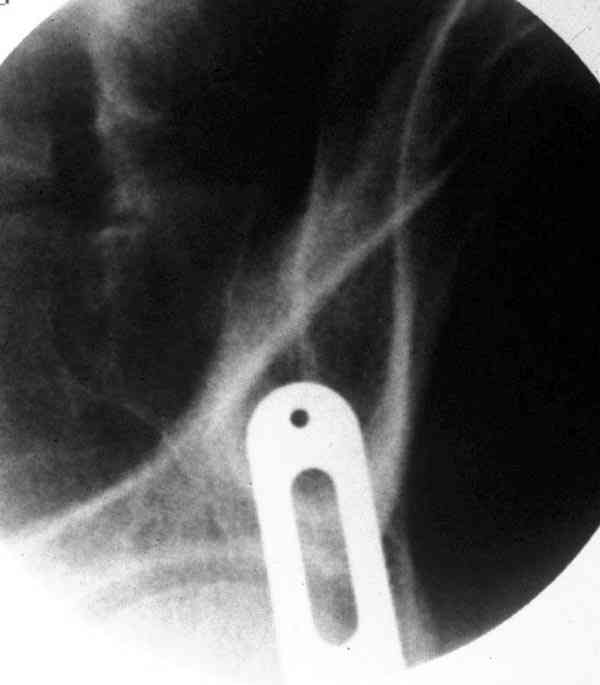

При свежем случае показана фиксация передней колонны к задней

(снимки), компрессирующим винтом минимальным перкутанным методом по

супраацетабулярной линии и в зависимости от состояния КПС.

Имя     : column fix.iliac view.jpg

Тип     : image/jpeg

Размер  : 37514 байтов

Описание: отсутствует

Url     : http://weborto.net:8080/pipermail/ortho/attachments/20070529/58a1e5fa/attachment-0005.jpg